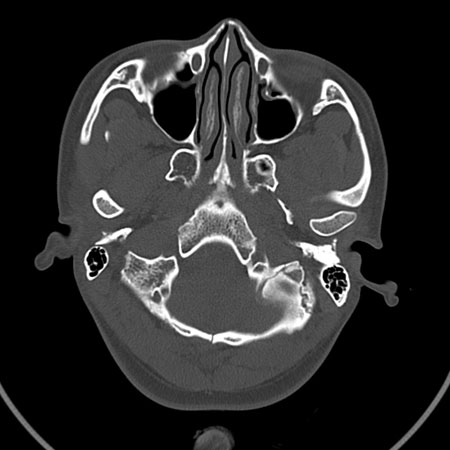

请问各位战友:图示箭头处是否为颅骨骨折?

病史:患者,女,20岁.头部及腹部外伤20分钟.伤后昏迷,无呕吐.头及右侧腰背部疼痛,双侧瞳孔等大,

右肾区叩痛.其它无异常.患者家属否认原有外伤史.

请大家看看是否为颅骨骨折.还是正常变异,或为陈旧骨折.谢谢.

图片未上传完,所见图象示枕骨线样低密度影,边缘锐利,结合外伤史,伤后昏迷,骨折不能除外。

枕骨的线样低密度影锐利、清晰,但正好位于矢状缝的位置,局部无明显软组织肿块,相临及对冲部位脑实质亦无出血及挫裂伤表现。

单就这几层暂不考虑骨折,建议上传完整图片。

楼主所关心的另一个线样影应该是头颅矢状面略偏左,射线正好穿过所致,不需要考虑骨折。

枕骨是单块的,矢状缝是在顶骨而不是在枕骨,枕骨后缘见线状低密度,边缘税利,考虑在骨折存在。

枕后部及左侧颞枕部边缘锐利的线样低密度影,局部软组织无异常,左侧乳突蜂房密度均匀,硬膜下及脑实质内未见出血灶,考虑为正常变异。

枕部考虑骨折。一般的颅逢不会跨越板障,楼主所示枕骨断面两侧板障也不连续。